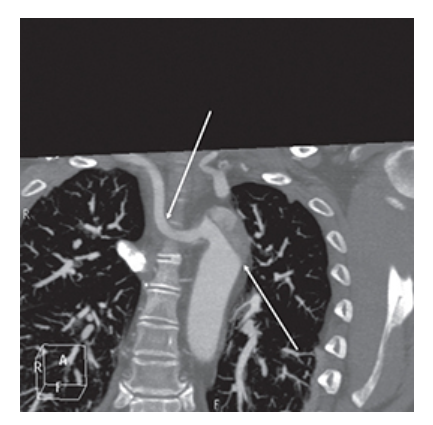

Aberrant Right Subclavian Artery. Coronal contrast-enhanced CT shows aberrant right subclavian artery (top arrow). Type B aortic dissection involving the descending thoracic aorta extending up to the left subclavian artery is also seen (bottom arrow).